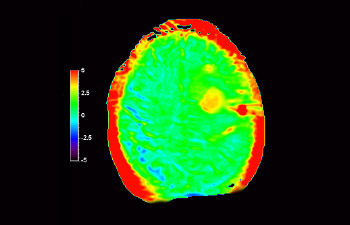

3D APT

Enhanced diagnostic confidence in neuro oncology